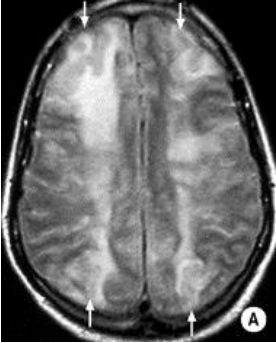

Case 4 Q# 1 of 4

• A 57 y/o man develops sudden left sided weakness while roller skating with his kids.

• Hx: he stopped taking his BP meds two weeks ago because they made him “feel weird.”

• Vitals : BP- 190/120, HR- 60, RR -12

• He has severe left sided weakness in his face, arm, and leg.

• The rest of his exam is normal.

• His MRI is attached.

What type of MRI is in the left image? The right image?

Left: T2W1 MRI. Right: DWI MRI.

Where in the brain is this man’s lesion located?

Within the right pons - the lesion has interrupted the tightly-packed fibers that are on their way to the brain’s motor cortex.

Without even looking at the MRI, what about this case suggests the lesion is NOT in the cortex?

He has face, arm, and leg weakness, but no sensory loss. If he had had a cerebral stroke massive enough to knock out that much of the motor cortex, it’s almost certain the neighboring sensory cortex (and likely Broca’s area) would be affected as well.

Given the location of the lesion, what type of blood vessel was likely involved? What was the pathogenesis behind the injury?

Lacunar (penetrating vessel) stroke. The ischemia was preceeded by hyaline arteriosclerosis.